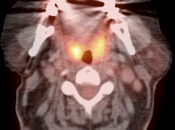

Unilateral FDG-Avid Tonsil (or Relative Increased Avidity of One Tonsil):

Special care is required when assessing the incidental finding of a unilateral hot tonsil (or relative increased uptake within one tonsil) — even though most unilateral hot tonsils are benign. Proposed techniques for assessment have included SUV threshold cutoff values, metabolic tumor volume assessment, and SUV ratios.

Unfortunately, it is advisable to raise at least a degree of concern for most FDG-avid unilateral tonsillar findings. The level of suspicion, of course, depends on the presentation.

At PETCTMD, we utilize the following practical approach for the incidental finding of a unilaterally FDG-avid tonsil: